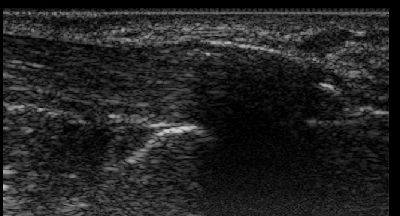

Fascite (img. 01) fascite 01